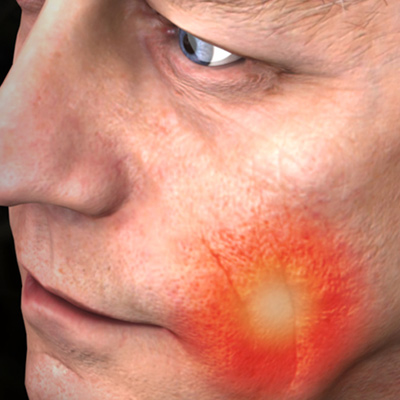

New Directions in Endodontics

Tuesday, April 2, 2024

This Compendium eBook features a continuing education (CE) article on the management of endodontic flare-ups. This eBook also includes an article on intentional replantation as a predictable and cost-effective option for preserving a natural tooth and as a favorable alternative to conventio...